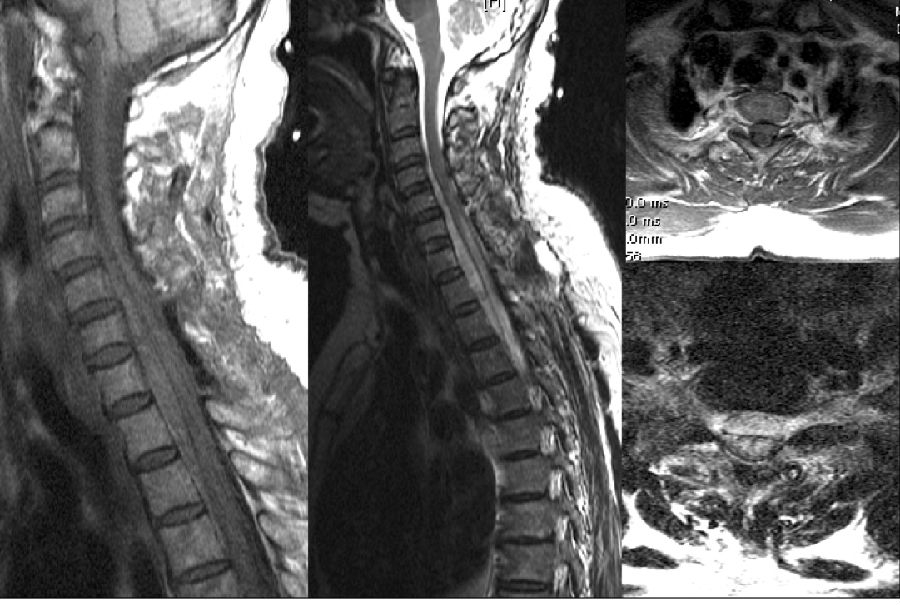

一、神经根损伤

病例一(轻度神经根损伤)

男,64岁。

主诉:左臀部伴左大腿后侧疼痛4年、加重3个月,间歇性跛行200米。

查体:左侧髂腰肌肌力IV级,左侧膝腱反射亢进。

手术:患者行UBE椎间融合+机器人置钉,左侧入路,术后双下肢麻木麻木,术后持续一个月的时间逐渐恢复。

病例二(重度神经根损伤)

女,34岁。

主诉:双下肢疼痛麻木4年、加重2个月。

查体:双下肢大腿后外侧、小腿外侧疼痛麻木,右下肢直腿抬高阳性。

手术:椎间盘完整切除。

术后:查体胫前肌、踇背伸肌力I级,术后康复锻炼一个月恢复正常。

病例三(马尾神经损伤)

男,62岁。

主诉:腰痛伴右下肢疼痛15年、加重1月,间歇性跛行200米。

查体:右侧直腿抬高及加强试验(+)。

手术:L3/4椎板减压+L4/5椎间融合+机器人置钉。

术后:双侧臀中肌腓骨肌无力,会阴区麻木。

术后6周,腓骨肌无力,右踝内翻的状态,右侧臀中肌无力,步行呈现“鸭步”。